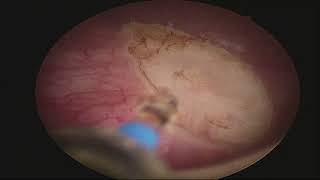

Enbloc resection of bladder tumour with thulium fibre laser (TFL laser) video

Enbloc Resection of Bladder Tumour with Thulium Fibre Laser(TFL)

Enbloc Resection of Bladder Tumour with Thulium Fibre Laser(TFL) Enbloc resection of bladder tumour with thulium fibre laser (TFL laser)

Enbloc resection of bladder tumour with thulium fibre laser (TFL laser) Enbloc Resection of Bladder Tumour with Thulium Fibre Laser

Enbloc Resection of Bladder Tumour with Thulium Fibre Laser Thulium Fiber Laser Enbloc resection of bladder tumour close to the ureteric orifice